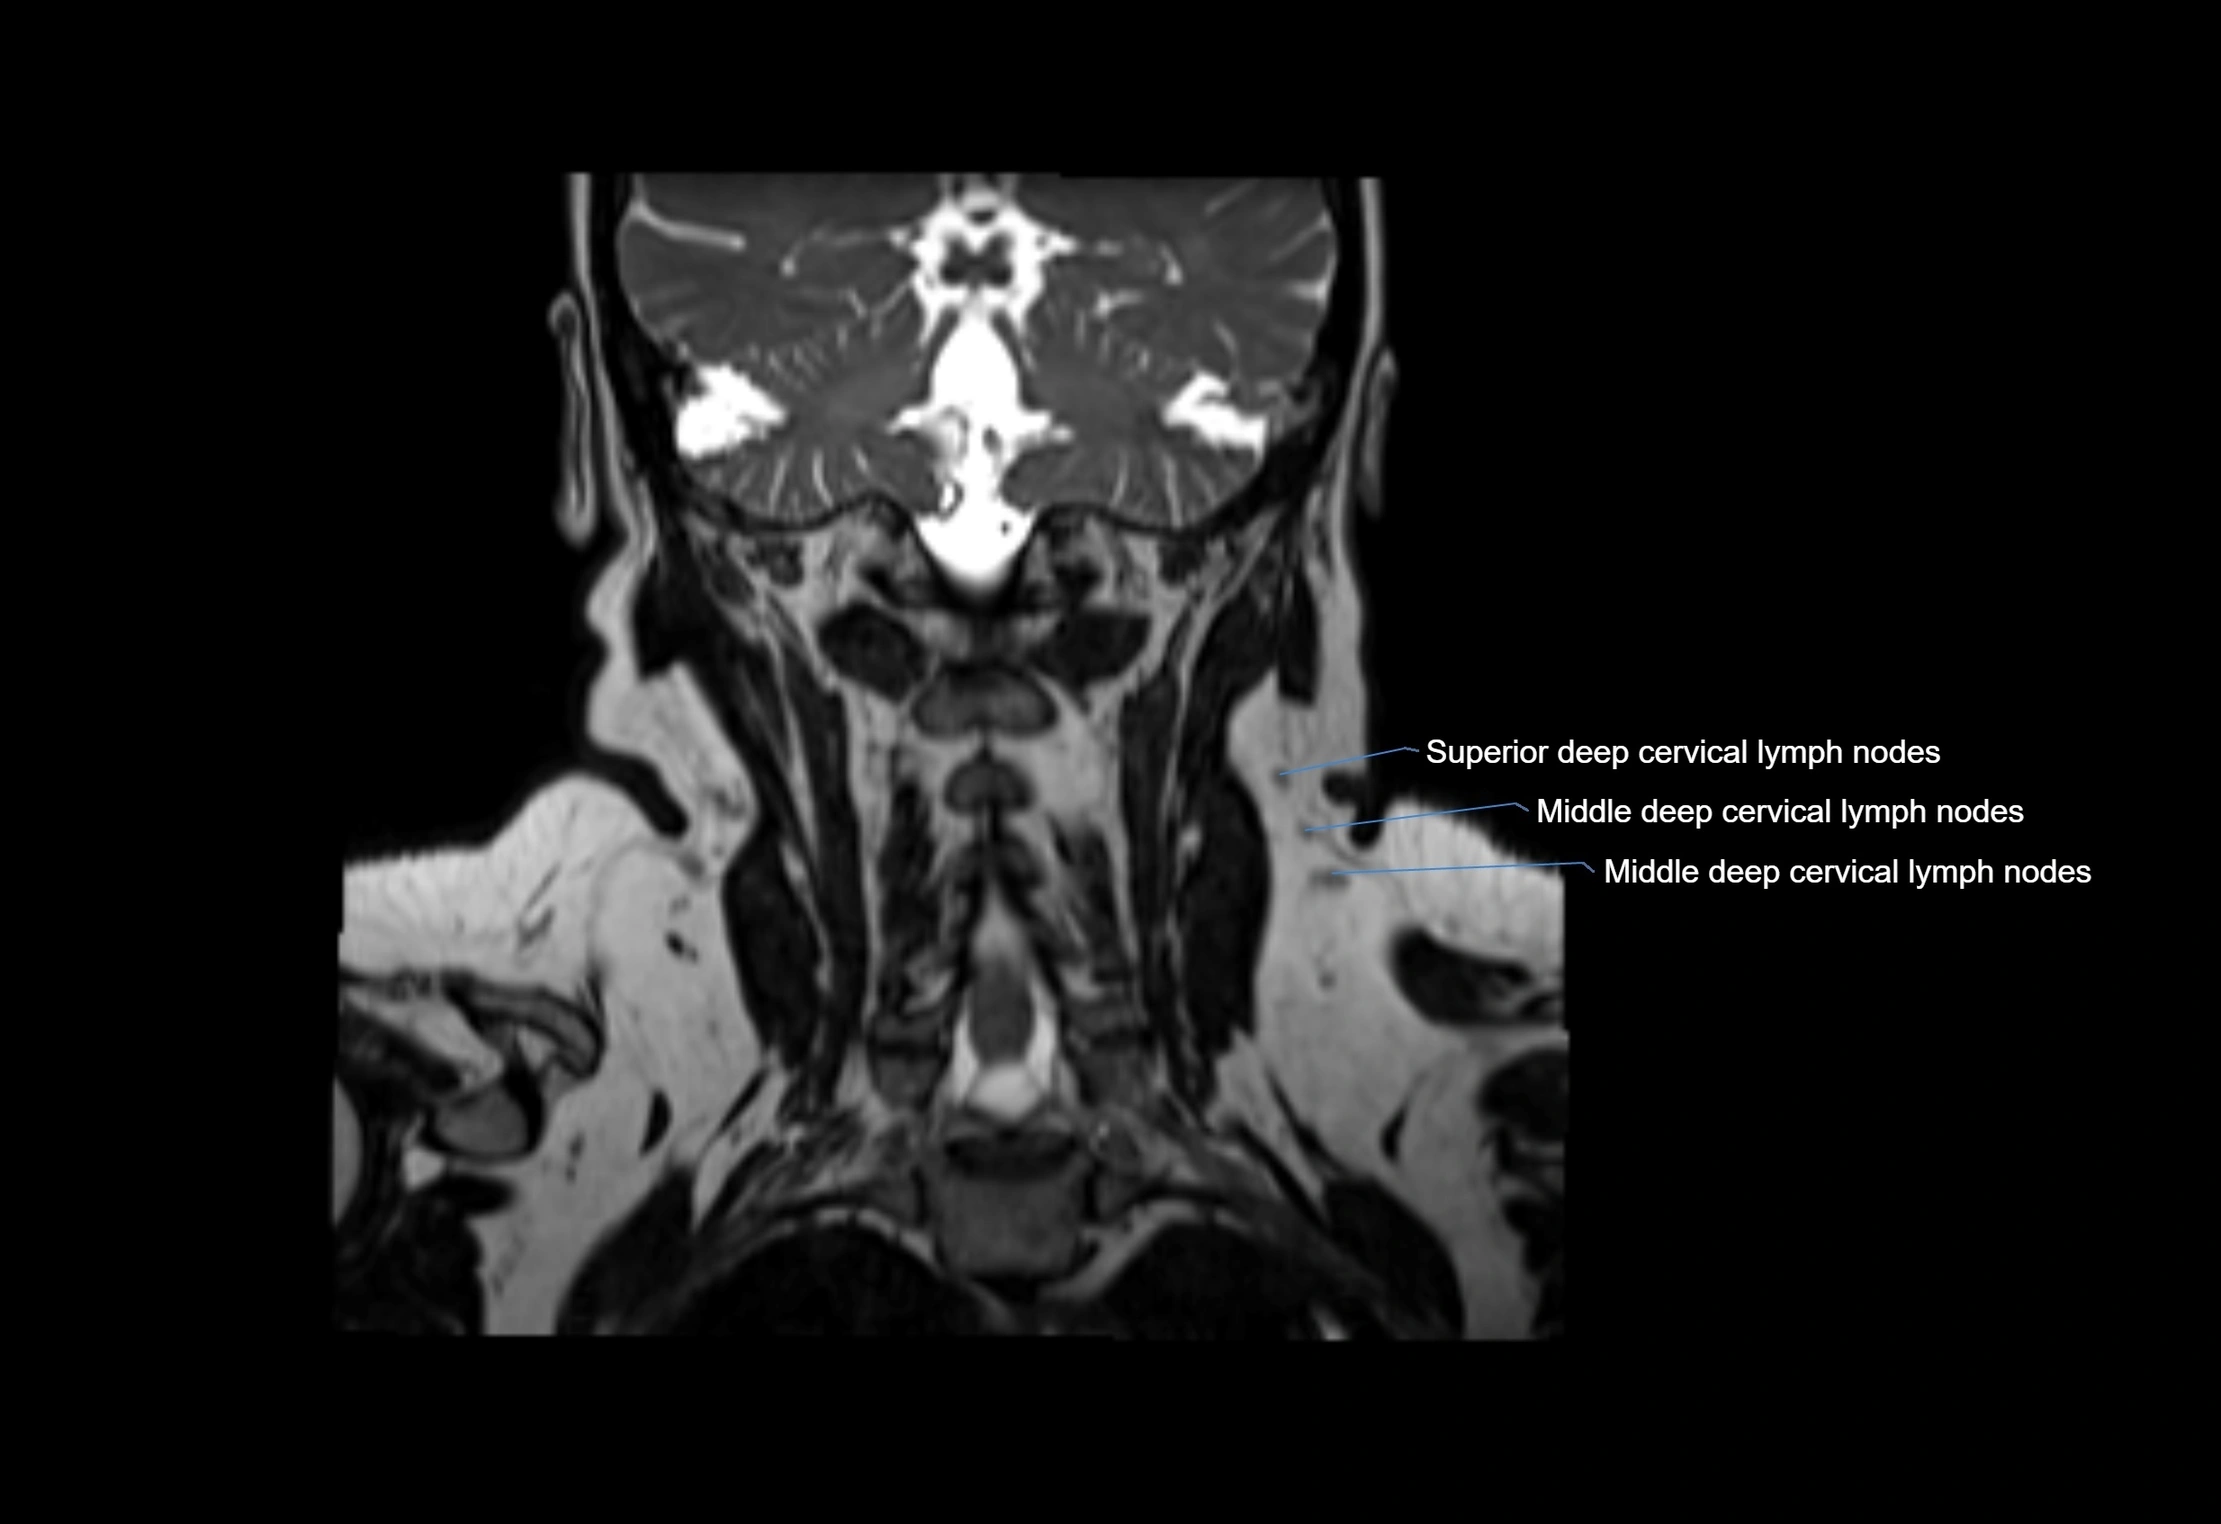

MRI Appearance

T1-weighted images:

• Normal accessory nodes appear as small, oval hypointense to intermediate signal structures within subcutaneous fat

• Surrounded by hyperintense fat, enhancing contrast for visualization

• Pathological nodes may appear enlarged or rounded, sometimes with cortical thickening

T2-weighted images:

• Nodes show intermediate signal, with surrounding fat bright

• Useful for detecting edema, inflammation, or infiltration

• Fatty hilum may appear slightly hyperintense relative to cortex

MRI images

image